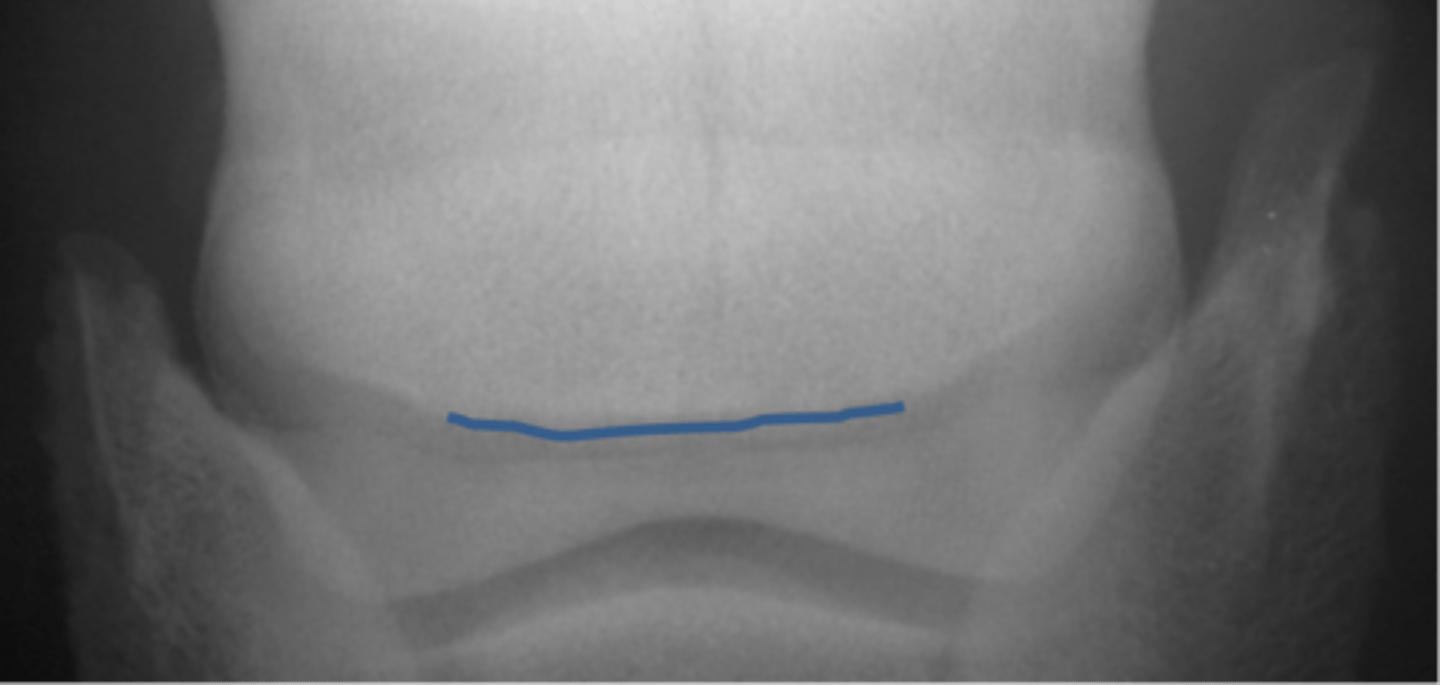

Navicular bone

Flexor cortex

Navicular bone

Proximal border of navicular bone

Distal border of navicular bone

Synovial invaginations

Flexor skyline

What view is this?

1. Flexor surface

2. Corticomedullary distinction

3. Number of synovial invaginations

What is the flexor skyline used to evaluate?

Navicular bone

Articular surface of navicular bone

Flexor surface of navicular bone

Sagittal ridge

Synovial invaginations